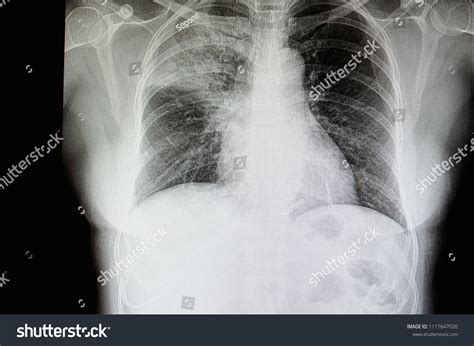

How Pneumonia Appears on an X-ray

Healthy lungs appear mostly black on an X-ray because they are filled with air. When pneumonia is present, the areas of the lung affected by the infection appear as opaque, white, or cloudy patches. This phenomenon is known as consolidation. It occurs because the air in the alveoli has been displaced by fluid, inflammatory cells, or debris, which blocks the passage of X-rays.

• Bronchopneumonia: This presents as patchy, diffuse opacities scattered throughout both lungs, rather than being confined to one area.